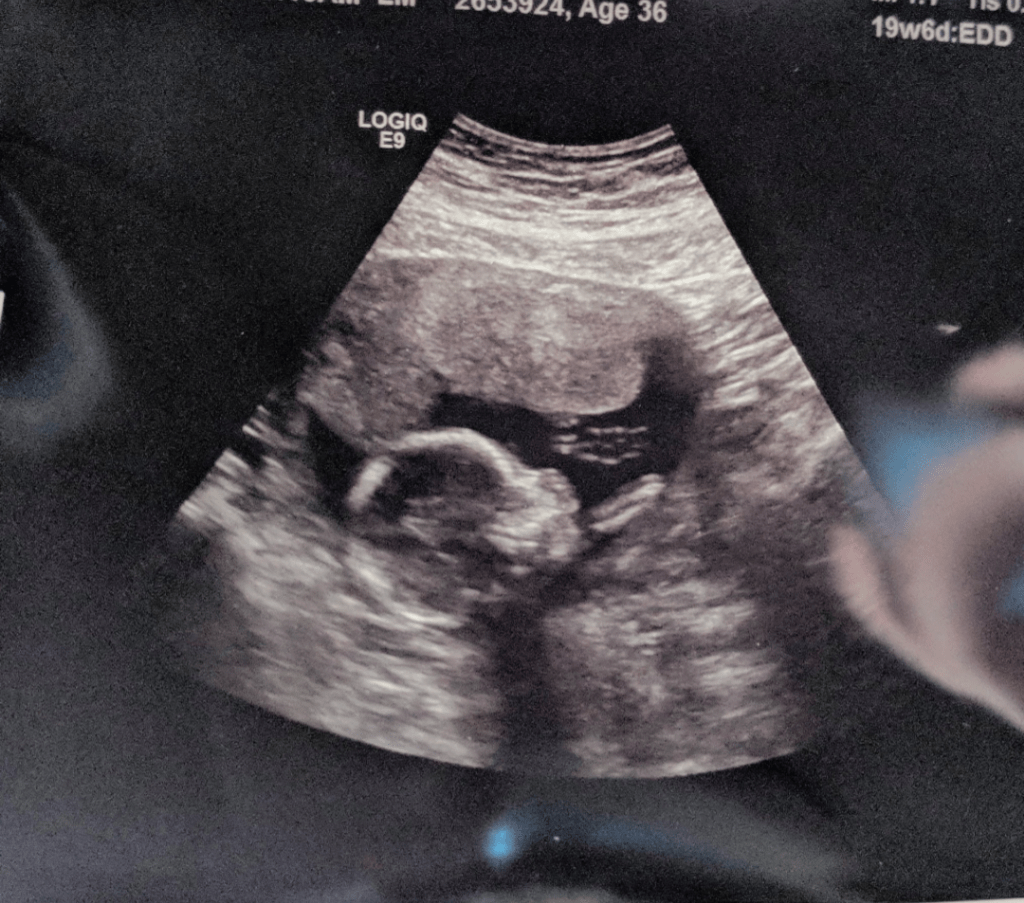

I decided to go the extra step and start with the Keto way of eating. I was eating under 20 net carbs a day. The first week I felt like garbage. By week 3 I had lost 17 lbs. Approximately one month after starting Keto, on December 22, 2017, I took a pregnancy test. I had taken so many tests in the last 2 years and none of them had been positive. As I cautiously peeked at the test I stopped breathing…there were 2 lines!!

It may sound crazy, but I was terrified. I hadn’t expected my body to respond to Keto quite so quickly. My body had just started to heal and I had no idea how to proceed. I did some research and the reviews were mixed. Some medical professionals were totally on board with low-carb eating during pregnancy, while other were completely opposed. I did find several women who had eaten low-carb very successfully during pregnancy, so I decided to take that route and adjust if needed.

I ate keto 75% of my pregnancy. Even though my healthcare providers were skeptical, they were impressed with my blood sugar and weight management. I ate tons of food and at 38 weeks pregnant weighed less than when I had started. I felt beautiful and healthy at the end of this pregnancy.

On August 24, 2018 my beautiful Violet was born, weighing 5lbs 11oz. I had never had a small baby before (3 over 10 lbs, 4 in the 9 lb range, and 2 in the 8 lb range.) I ended up with a c-section. Little Miss decided to be breech and I had pre-eclampsia. Her birth was more complicated than expected, but this body that was in the process of healing gave birth to a beautiful baby girl – my Keto baby, #10.